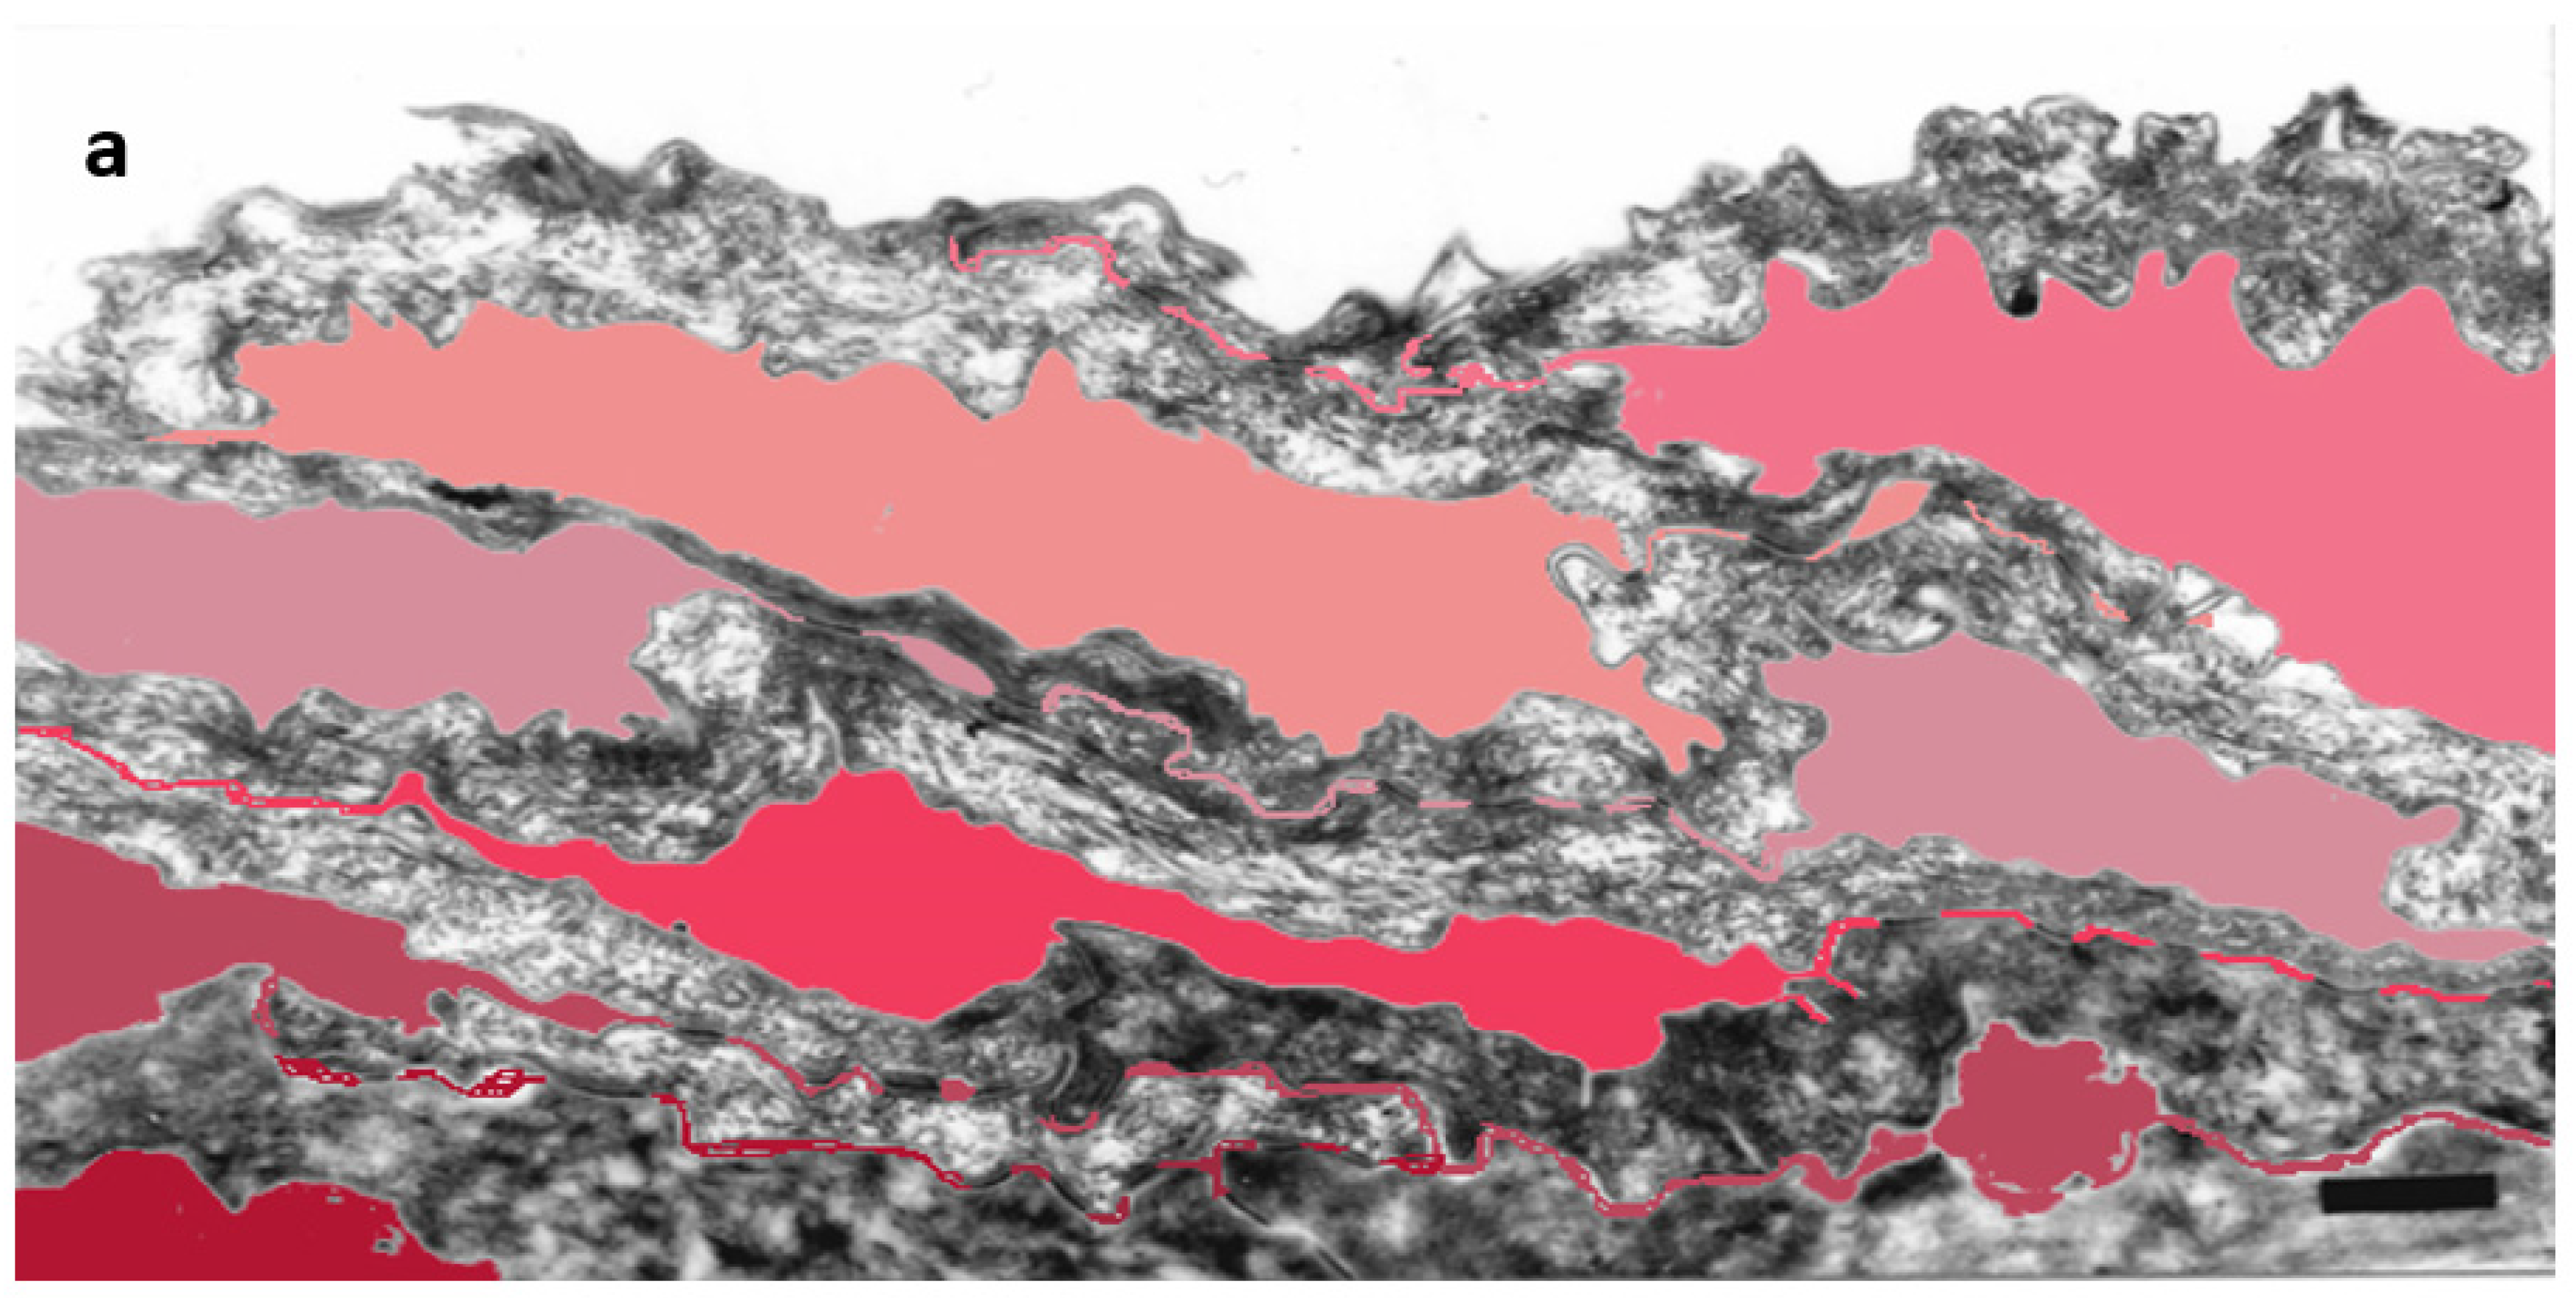

Figure 4.

Ultrastructural features observed in the SC of PSD include paucity of corneodesmosomes (d) that rapidly disappear from the lower parts of the horny layer, as seen in (a), and upregulation of expression of TJ-derived intercorneocyte “fusions” (arrows). (b) In the upper SC, the remaining corneodesmosomes (d) are often found in the proximity of the TJ-derived riveting structures (arrows). Bars = 1 µm in (a); 0.5 µm in (b).

The cell–cell fusions of lipid envelopes in the upper part of the lateral intercorneocyte contacts, which have been shown to result from the persistence of TJ structures, were quantified and the results compared with the situation in 35 normal controls (Table 4).

Fraction of the apical-lateral contacts between corneocytes showing “fused” morphology in the SC of PSD. NHS = normal human skin.

Upregulation of the TJ-derived corneocyte envelope fusions in PSD may represent a compensatory phenomenon in face of corneodesmosome fragility. It may contribute to cohesion in the upper SC directly, through enhanced cell–cell adhesion, and indirectly, by hindering access of extracellular hydrolytic enzymes to corneodesmosomes.

Mature upper SC is more rigid than living epidermis and lower, freshly cornified keratinocytes [40]. In this situation, minor mechanical insults to tissue lacking reinforced corneodesmosomes may provoke a preferential split at the interface between the two parts. The upper part of the horny layer of PSD appears to be reinforced by the increased presence of cross-linked TJ remnants.